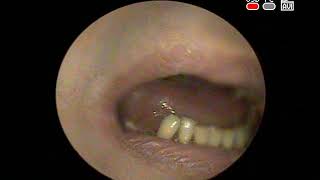

Введение в оториноларингологию. История развития оториноларингологии.

Лекция для студентов, клинических ординаторов, аспирантов медицинских ВУЗов.

Кафедра Оториноларингологии МГМСУ

Практические навыки. ОНМедУ. Кафедра Оториноларингологии.

Кафедра Оториноларингологии Оториноларингология с доктором Осипенко. Лицевые, шейные боли при заболевании лор-органов